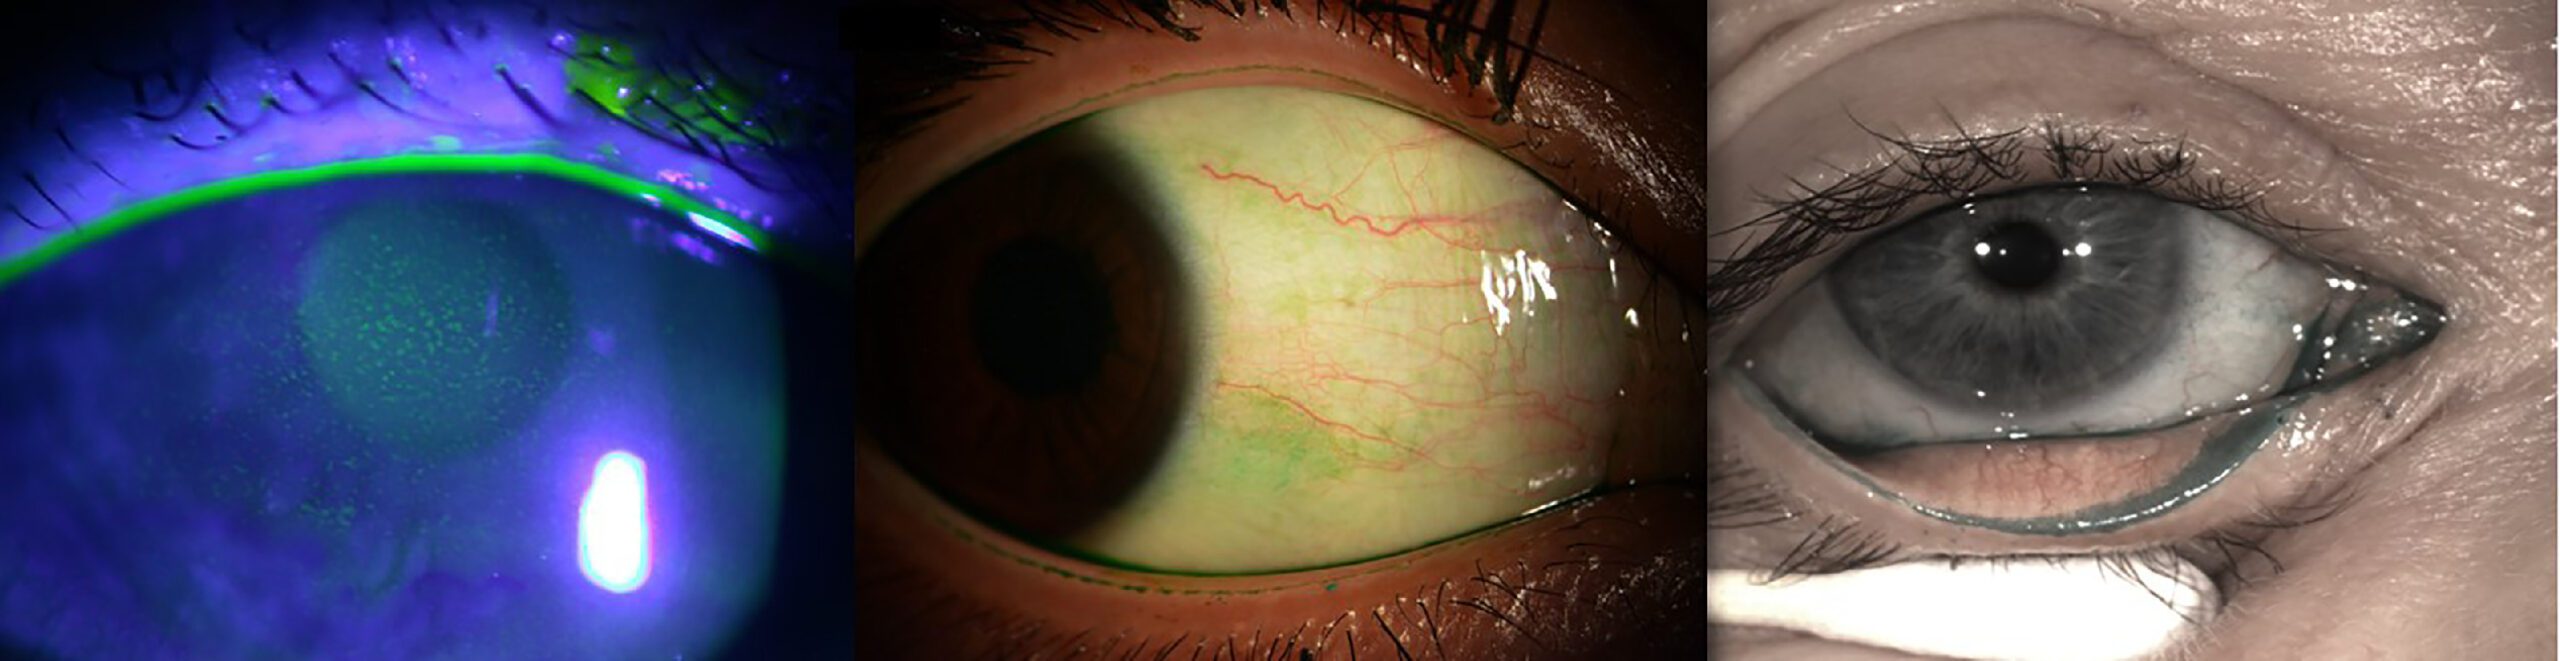

L-R: Fluorescein corneal staining illuminated with a blue light; lissamine green bulbar conjunctival staining under white light; lissamine green staining of lower lid wiper epitheliopathy under white light (courtesy TFOS DEWS III report)

But setting up a dry eye clinic doesn’t necessarily require a heavy investment initially; you most likely already have the basics, i.e. a slit lamp and fluorescein, add in lissamine green and you have all the basics required to diagnose DED according to the TFOS DEWS III Diagnostic Methodology Report2.